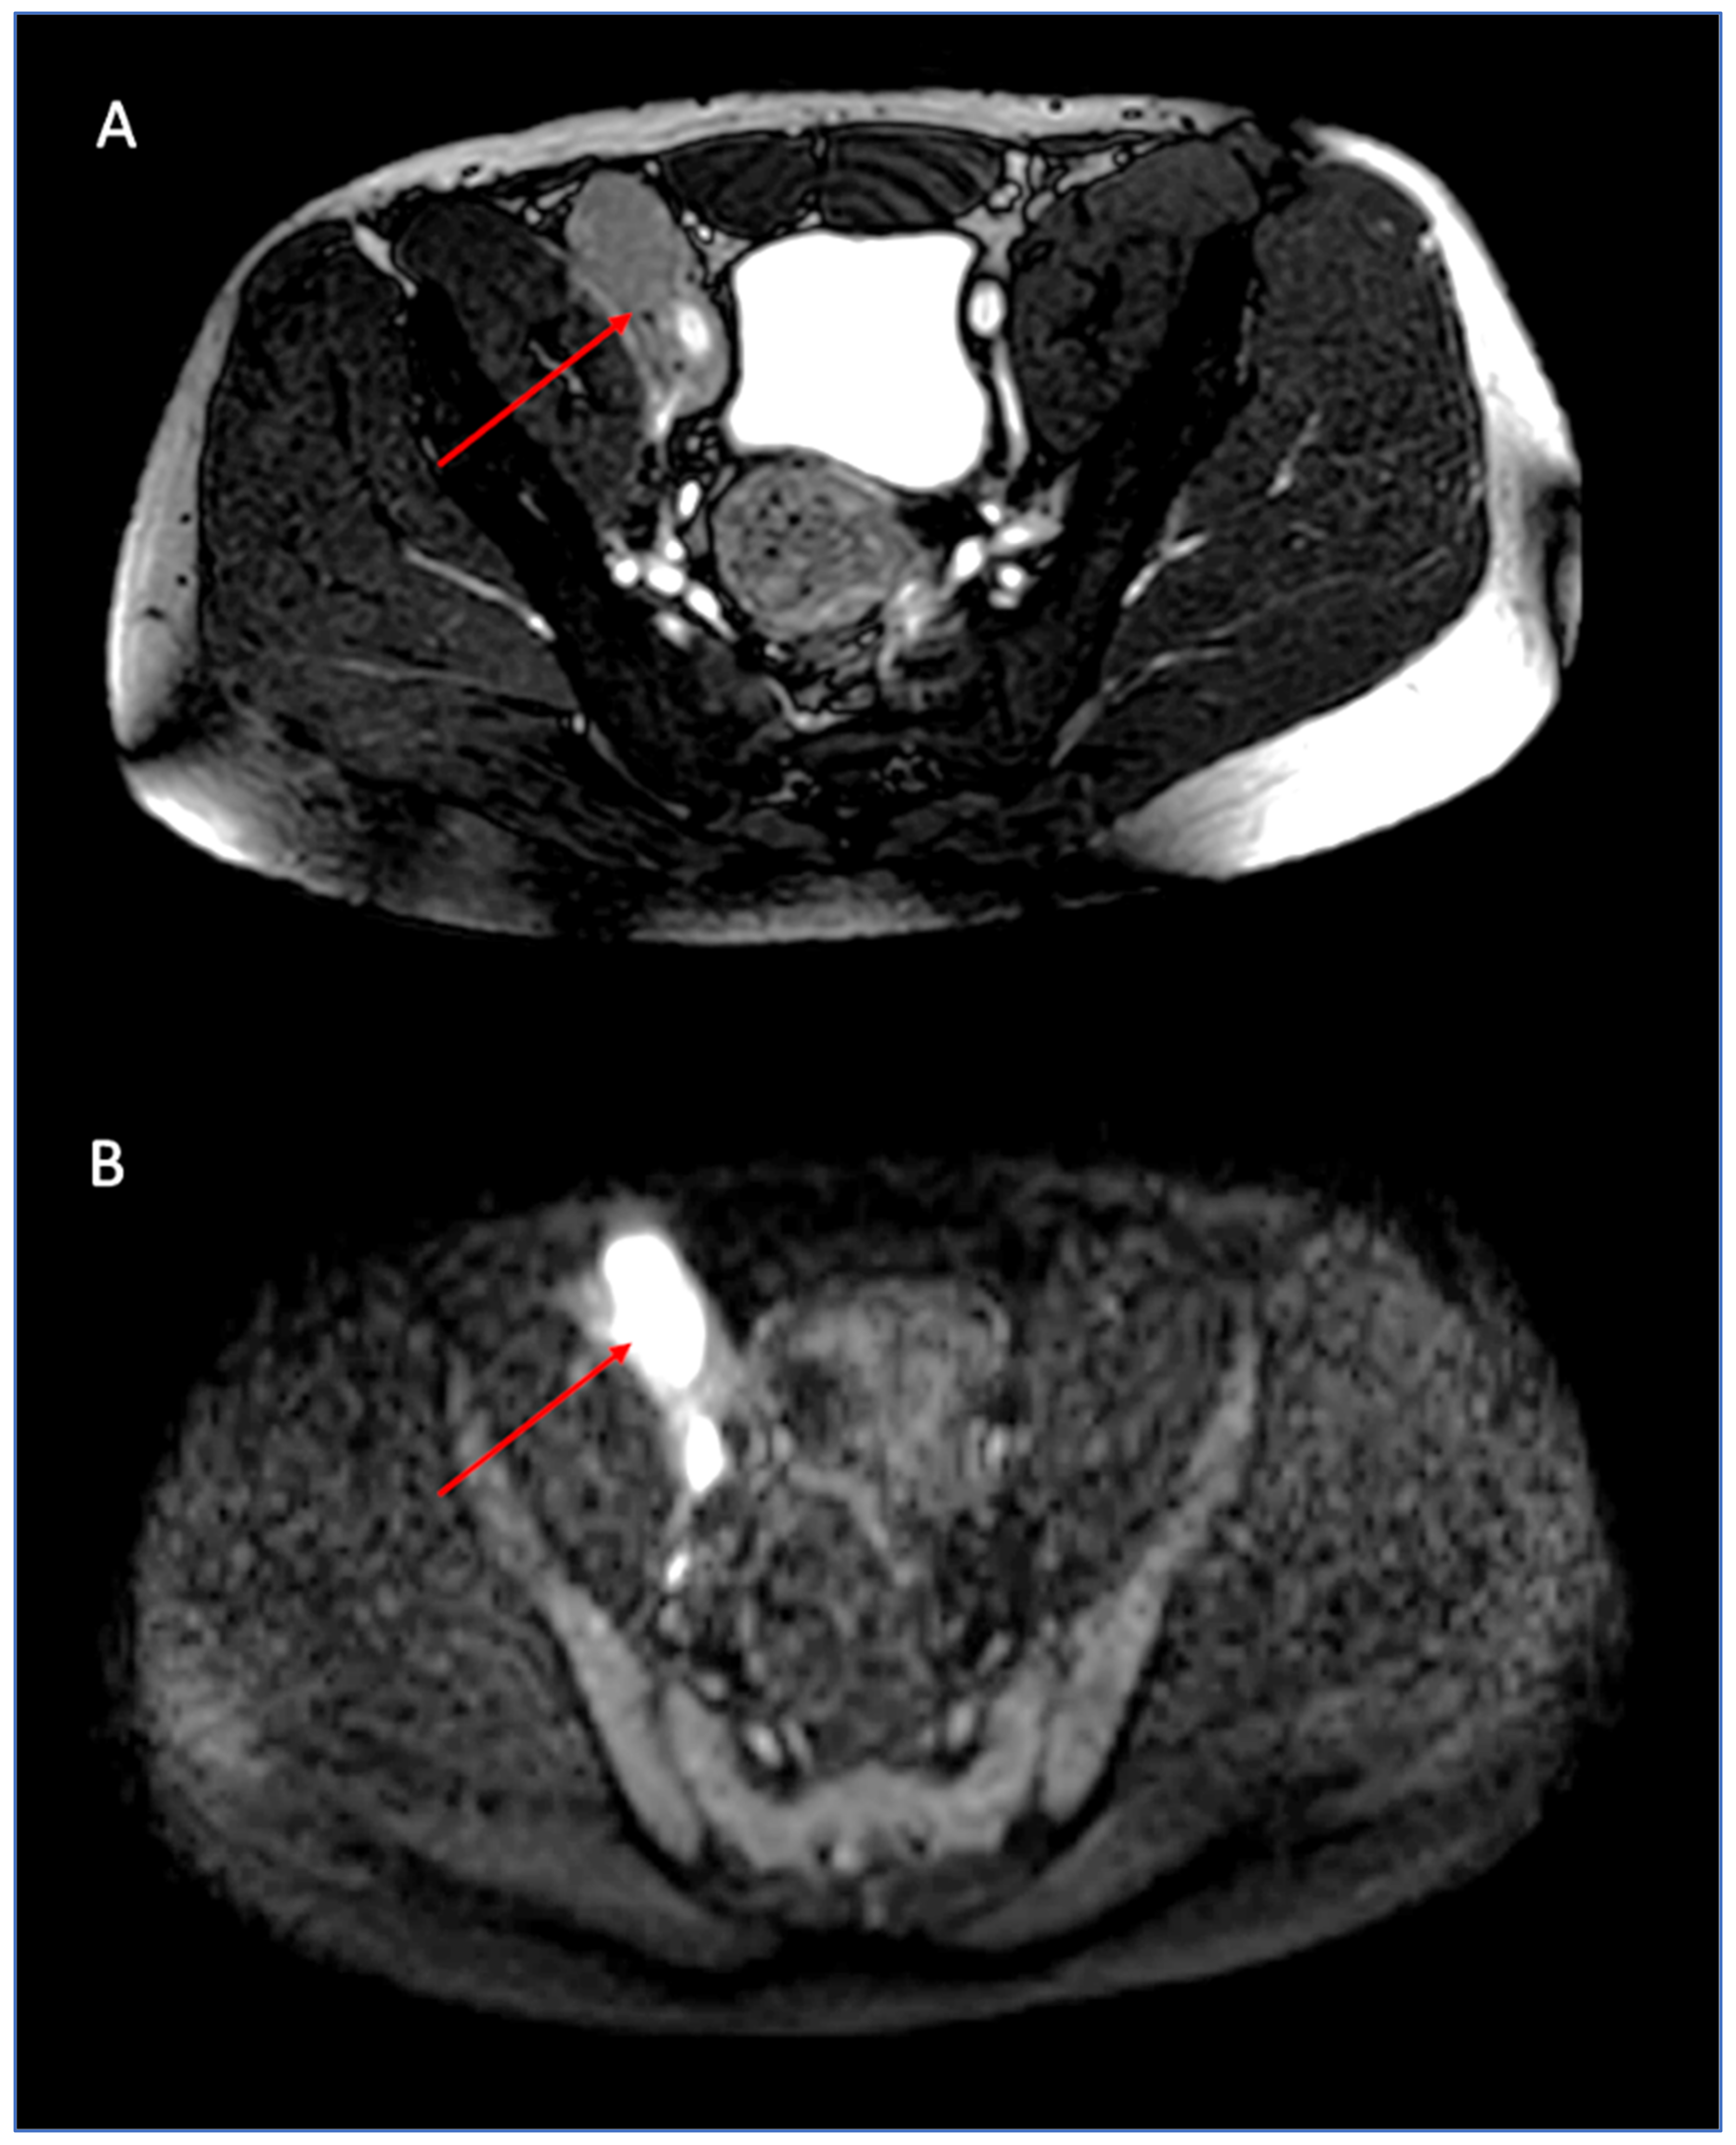

2. Case Report